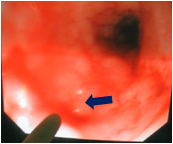

EA/TEF术后常见并发症和治疗

吻合口漏

胃食管反流

吻合口狭窄

气管软化

食道气道瘘复发